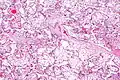

| Micrograph of villous immaturity. H&E stain. | |

Immature chorionic villi are larger and have more central blood vessels; thus, the diffusion distance for gas and nutrient exchange is larger and, therefore, placental function is impaired.